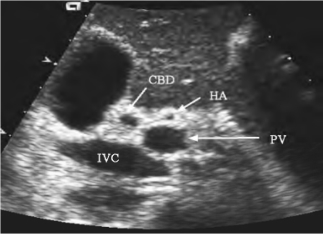

1.29.1一、胆管系统的解剖

1.29.3三、正常超声表现